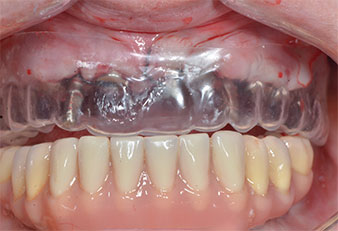

Three years later it was time for a maxillary denture of the same type. Based on CBCT planning sinus augmentation was avoided with the aid of short implants, and a surgical template was used to transfer the planned positions to the alveolar ridge (Figs. 1 and 2).

Due to the relatively hard bone (D2) in this area, the 10 mm long implant sites at positions 11 and 21 were finalized with a 4 mm diameter rotary drill, in combination with a W&H WS-75 L surgical contra-angle handpiece, the W&H Implantmed implant motor and the optional W&H Osstell ISQ module. In contrast, due to the soft bone the posterior sites were prepared to a final 3 mm diameter using the Piezomed I3P instrument. The implants were finally placed transgingivally to osseointegrate for three months (Figs. 6-10). The existing denture was retained on four provisional implants (Fig. 8).